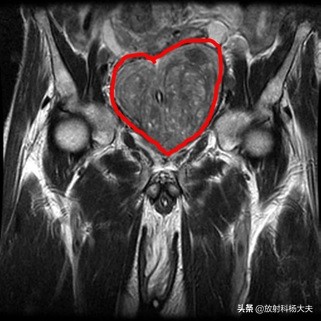

“有时候,又很温馨。”

比如,作为一个单身狗,在七夕,收到来自患者增生前列腺的比心